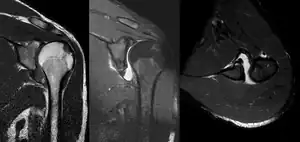

A diagnosis of shoulder dislocation is often suspected based on the person's history and physical examination. Radiographs are made to confirm the diagnosis. Most dislocations are apparent on radiographs showing incongruence of the glenohumeral joint. Posterior dislocations may be hard to detect on standard AP radiographs, but are more readily detected on other views. After reduction, radiographs are usually repeated to confirm successful reduction and to detect bone damage. After repeated shoulder dislocations, an MRI scan may be used to assess soft tissue damage. In regards to recurrent dislocations, the apprehension test (anterior instability) and sulcus sign (inferior instability) are useful methods for determining predisposition to future dislocation.

A Hill–Sachs lesion is an impaction of the head of the humerus left by the glenoid rim during dislocation.[5] Hill-Sachs deformities occur in 35–40% of anterior dislocations. They can be seen on a front-facing X-ray when the arm is in internal rotation.[8] Bankart lesions are disruptions of the glenoid labrum with or without an avulsion of bone fragment.